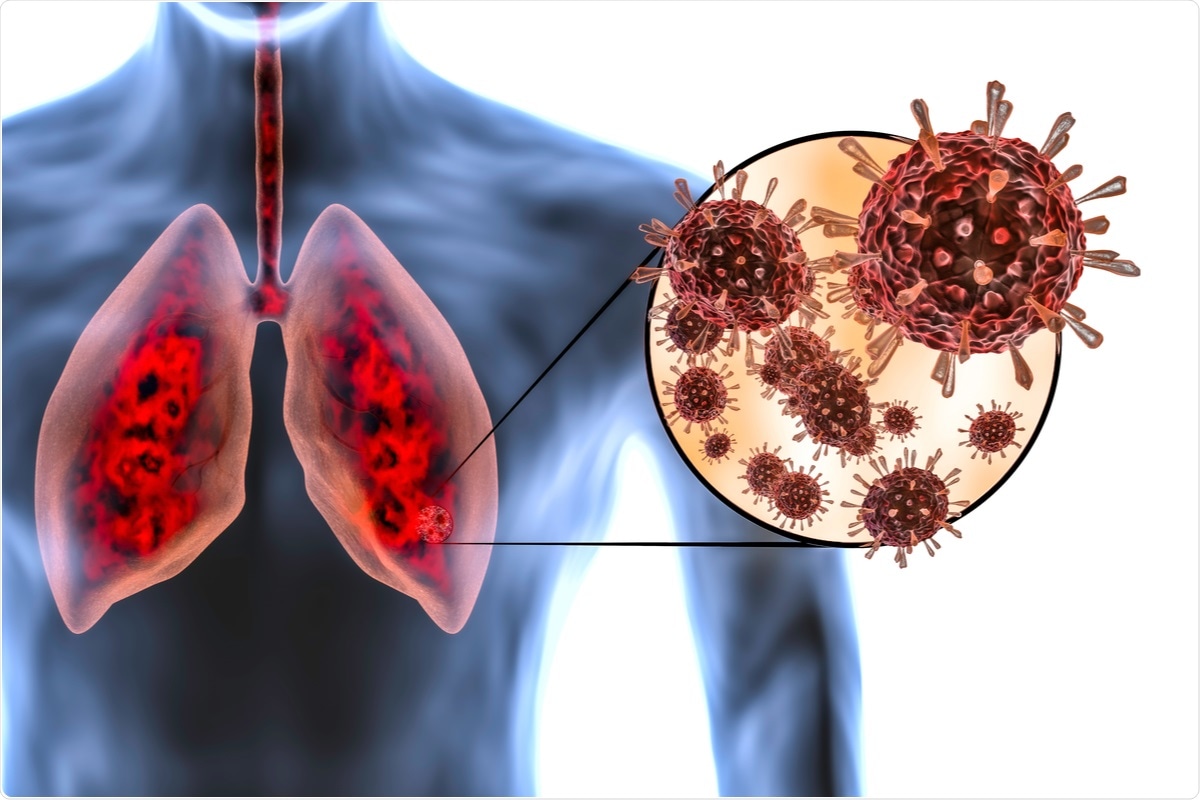

ကိုဗစ်ရောဂါဟာ အသက်ရှူလမ်းရောဂါတခုဖြစ်တယ်။ အဆုတ်တွေ ပျက်စီးစေတယ်။ သာမန်လောက်နေ ဆိုးဆိုးဝါးဝါး ခံစားရနိုင်တယ်။ တချို့ အသက်ဆုံးပါးရတယ်။ အသက်ကြီးသူတွေ၊ နှလုံးရောဂါ၊ ဆီးချိုရောဂါ၊ ကင်ဆာအခံရှိသူတွေ၊ ကိုယ်အလေးချိန်များပြီး ကိုလက်စထောများသူတွေမှာဖြစ်ရင် ဆိုးတယ်။

ပိုးတွေက အမြန်ပွါးလာမယ်။ အသက်ရှူလမ်းအောက် ဆက်ဆင်းမယ်။ လေပြွန်ကြီးတွေ၊ အဆုတ်နှစ်ဘက်။ အဆုံးနေရာကို Alveoli လေအိတ်လို့ခေါ်တယ်။ လူတိုင်း အဲဒီနေရာမှာ သွေးထဲက ကာဘွန်ဒိုင်အောက်ဆိုဒ်နဲ့ အသက်ရှူတဲ့လေထဲမှာပါလာတဲ့ အောက်စီဂျင် အပြောင်းအလဲလုပ်တယ်။

ကျန် ၂၀% ကတော့ ဆိုးတယ်။ အဆုတ်ရောင်လာပြီ။ Pneumonia နူမိုးနီးယားလို့ ခေါ်တယ်။ Alveoli လေအိတ်သေးသေးလေတွေ ရောင်မယ်။

တကယ်ဆိုးတာက ၁၄% သာရှိပါတယ်။ အဆုတ်နှစ်ဘက်လုံး နူမိုးနီးယားဖြစ်မယ်။ အဆုတ်ထဲမှာ အရည်တွေ ပြည့်နေမယ်။ မောမယ်။ အသက်ရှူမဝဖြစ်မယ်။ အသက်ရှူမြန်မယ်။ Oxygen အောက်စီဂျင်လိုတယ်။ Ventilator အသက်ရှူစက်လိုတယ်။

အရေးပေါ်အဆင့်လူနာ ၅% သာရှိတယ်။ Severe pneumonia နဲ့ acute respiratory distress syndrome (ARDS) လို့ခေါ်တယ်။